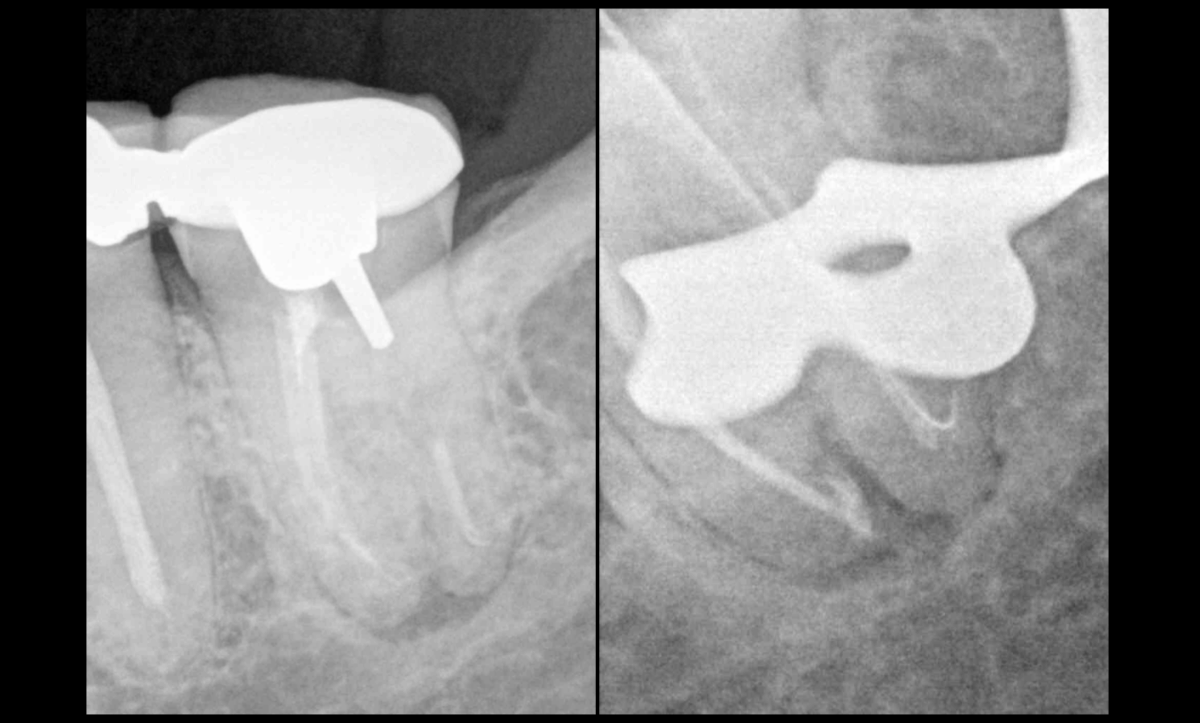

Courbures et limes manuelles

❓𝐂𝐨𝐦𝐦𝐞𝐧𝐭 𝐠𝐞́𝐫𝐞𝐫 𝐚𝐮𝐭𝐫𝐞𝐦𝐞𝐧𝐭 𝐪𝐮’𝐚𝐯𝐞𝐜 𝐝𝐞𝐬 𝐥𝐢𝐦𝐞𝐬 𝐦𝐚𝐧𝐮𝐞𝐥𝐥𝐞𝐬 𝐜𝐞 𝐠𝐞𝐧𝐫𝐞 𝐝𝐞 𝐜𝐨𝐮𝐫𝐛𝐮𝐫𝐞𝐬 ❓

🦷 ➡️ Pas moyen de gérer cela autrement qu’avec des limes manuelles !

BLOG - Dr Brice Riera - Endodontie - courbures et limes manuelles